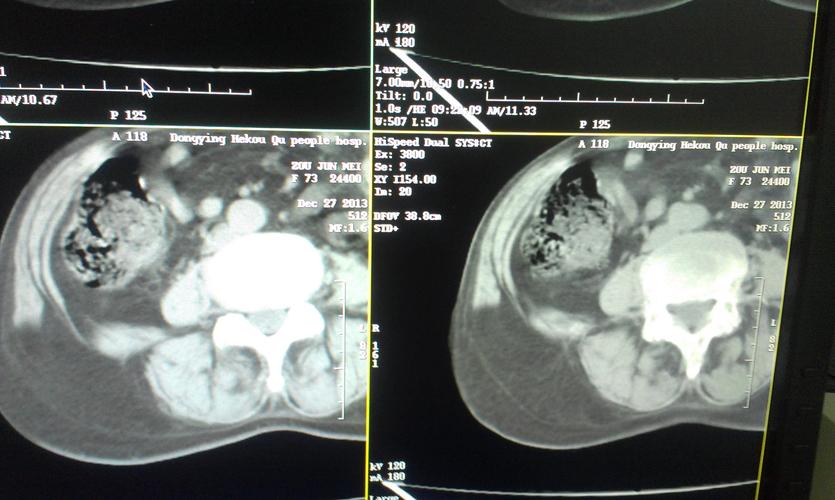

我院疝外科团队完成粤西首例完全腔镜下急诊嵌顿性腰疝tapp修补术